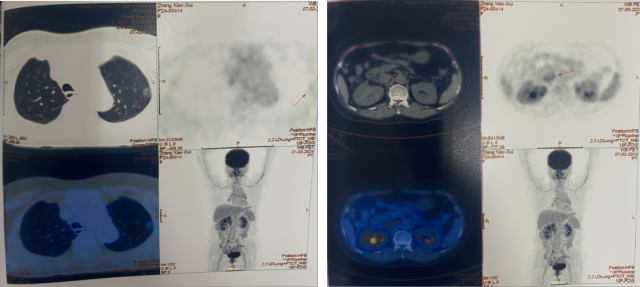

CT(2022.7):1. 右肺转移瘤切除术后改变;2. 左肾上腺结节,转移?3. 左肾多发结节,转移瘤?4. 腹膜后淋巴结肿大,转移可能;5. 左肾多发小囊肿。

2022.10 开始予以靶免联合治疗

PETCT(2022.10):1. 左侧肾上腺结节灶,糖代谢增高,转移瘤可能性大;2. 左肾多发结节状突起,糖代谢增高,考虑转移瘤,需结合增强 CT 综合判断;3. 右下肺切除术后,术区未见复发;4. 右侧胸壁局部增厚、糖代谢增高,术后改变?建议追踪。

靶免联合治疗 1 年后复查

CT(2023.7.17):1. 左肾上腺结节、左肾结节及肿块较前明显增大:转移?左肾 CA 并左肾内、肾上腺转移?2. 腹膜后淋巴结较前增大,转移可能;3. 余况基本同前。